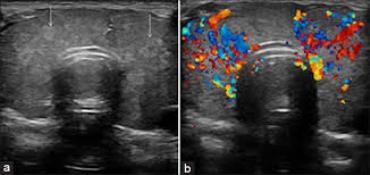

At Ultracare Diagnostic, we understand the importance of your health and the essentiality of accurate diagnosis. Therefore, we offer you comprehensive care and a non-invasive Ultrasound test that helps determine how well your body organs are functioning and if there are any abnormalities present. This helps the doctor to provide you with an accurate diagnosis and treatment for the same

We offers Best Services With Experienced hand on Sonology